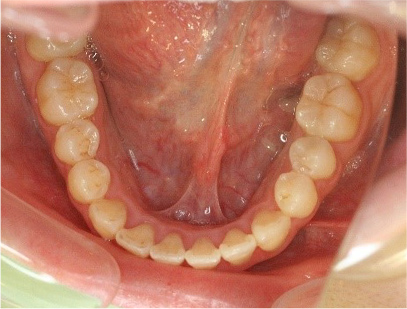

• 下側